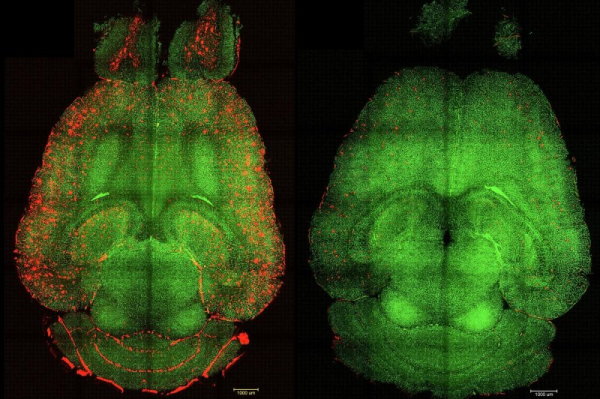

Before-and-after fluorescence microscope images of a mouse brain show red-colored build-ups of toxic amyloid beta plaque (L) and the same brain 12 hours after being treated with nanoparticles. Spanish and Chinese scientists say their nanoparticle experiments could create a new focus on the blood-brain barrier in treating Alzheimer's disease. Image courtesy Institute for Bioengineering of Catalonia

Лише через годину після серії ін'єкцій наночастинок «ми спостерігали зниження кількості бета-амілоїду в мозку на 50-60%», – заявили автори, додавши, що миша-піддослідна, яка за людським поняттям була еквівалентна 90-річній і була генетично запрограмована на високий рівень бета-амілоїду, демонструвала нормальну поведінку через шість місяців після лікування, включаючи зворотне зниження когнітивних функцій та пам'яті.